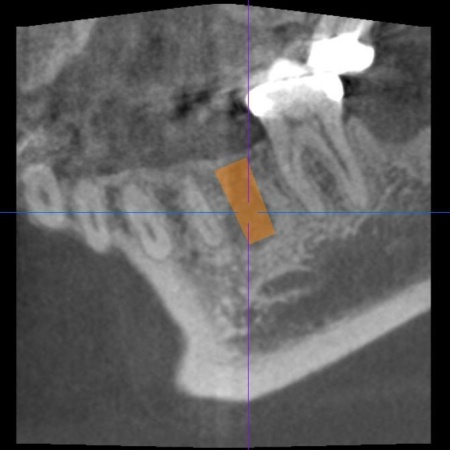

| 診断 | 拝見したところ、左上奥歯(第1小臼歯)は歯の上の部分である歯冠が折れ、歯根のみ残っている状態でした。 また、左下奥歯(第2小臼歯)には被せ物が装着されています。 レントゲン撮影をして痛みの原因を詳しく検査したところ、左上下奥歯の歯根が割れており、その影響で痛みが出ていると考えられました。 歯根が割れた歯は温存が難しく、このまま放置すると炎症が広がって周囲の歯に悪影響を及ぼすおそれがあるため、抜歯せざるを得ない場合があります。 以上のことから、温存が難しいと判明している左上奥歯は抜き、左下奥歯は被せ物を取り外して内部を確認したうえで、適切な処置を行うことが望ましいと診断しました。 |

| 行ったご提案・治療内容 | 診断結果をお伝えし、患者様の了承を得たうえで左下奥歯の被せ物を外したところ、レントゲン検査での診断どおり、歯根が割れていることが確認できました。 そのため、患者様には左上下奥歯とも温存が難しい旨を説明し、抜歯に同意いただきました。 患者様は、以前当院で人工歯根を顎の骨に埋入して歯を装着するインプラント治療を受けていたため、今回も左上下奥歯ともインプラント治療を希望されています。 メリット デメリット 改めてメリットとデメリットをしっかりお伝えしたところ、インプラント治療に対する不安はないとのことで、治療に同意いただきました。 まず、左上下奥歯を慎重に抜きます。 インプラント手術後は経過観察を行い、インプラントが顎の骨に結合したことを確認したら、インプラント上部に取り付ける人工歯を作製するために精密な型取りを実施します。 後日、完成した人工歯をインプラントに装着し、使用感や見た目に問題がないことを確認して、治療を終了しました。 |